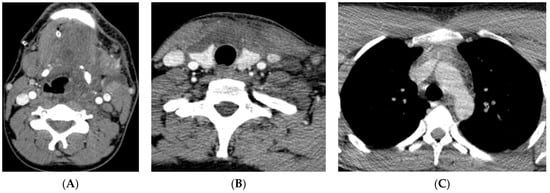

| Neck CT | Pus collection - in the left submandibular area - around the hyoid bone - around the left piriform recessus - around the thyroid cartilage - around the sternocleidomastoid muscle | Presence of a gas collection with delamination of the soft tissues of the neck in the area of the parapharyngeal space on the left Gas collections in - both palatine tonsils - anterior cervical space - left carotid space up to the level of the aortic arch - bilateral submandibular and sublingual space | Multiple air collections that stratify the tissues of the neck on the right side | Multiple air collections that stratify the superficial and deep tissues of the neck and enter the mediastinum |

| Chest CT | pus collection: ventral from the thyroid gland measuring 68/14 mm, with a density of 34–40 HU reaching the carina | Purulent collection starting from the neck and reaching the anterior mediastinum above the carina, presence of gas collections | Multiple air collections involving all departments of the anterior mediastinum above the carina | Massive pneumomediastinum, presence of fluid-purulent collections in the anterior and posterior lower mediastinum below the carina |